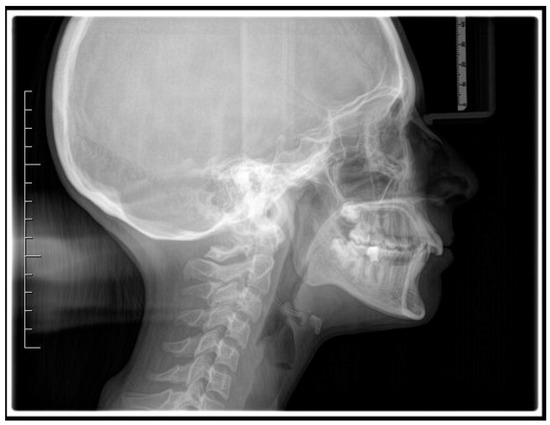

Figure 2.

Pre-treatment lateral teleradiography.

A case of CA therapy without attachments and without the aid of hybrid elements has been documented. The patient, an 18-year-old woman at the beginning of treatment (October 2021), signed written informed consent to orthodontic treatment and authorized the use of her anonymized treatment data, including photos, X-rays and virtual models of the dental arches. She needed to rehabilitate two edentulous areas corresponding to first maxillary and mandibular molars, both on the left side, assessed as irrecoverable for destructive caries at the time of the orthodontic evaluation (Figure 1). The patient refused rehabilitation with prosthetic implants and orthodontic treatments with fixed or hybrid fixed-removable therapy. Orthopanoramic (Figure 1) and lateral teleradiography of the skull (Figure 2) were acquired to make the necessary assessments. The cephalometric examination was performed using the Cephio© Cephalometric Analysis artificial intelligence driven platform (Cephio sp. z. o. o. [Ltd.]). Her skeletal class II malocclusion was due to maxillar and mandibular retrusion (SNA 80°, SNB° 74.6°, ANB 5.4°, SNPog 76.2°). She had “long face” (OP-SNP 21.1°), a posterior inclination of the jaw (MPGoGn- SNP 35.4°), slight hyperdivergence (FMA 26.2°), with pro-inclined lower incisors (1-NB 28.4°, IMPA 96.1°) and retroclined upper incisors (1-NA 14.1°, FMIA 57.7°). Overjet and overbite were severely altered (6 and 7 mm) (Table 3). Orthodontic treatment started 4 months after the first left maxillary and mandibular molar extractions. Intraoral and facial photos were captured (Canon© Coolpix A900, Canon, Tokyo 146-8501, Japan). Dentally, she had a first molar and canine class on the right side, and a first canine class on the left side in which the molar class was no longer assessable (initially it was a first class); however, a partial reduction in edentulous spaces was observed due to the movement of adjacent teeth (Figure 3) and lower incisors were moderately crowded. Precision silicone impressions (Elite HD+ Putty Soft Normal and Elite HD+ Super Light Body, Zhermack SpA, Badia, Italy) were taken using the double technique. Then, a virtual setup of the treatment with CAs was developed to evaluate its feasibility. It showed full closure of edentulous spaces and was also discussed successively with the patient. The orthodontist clarified there were no data from the literature (at that time) to support the successful movements required with only CAs. The orthodontist and patient started treatment by agreement. The informed consent to treatment was signed. It also covered clinical re-evaluation with solutions less favorable to the patient’s preferences if the results in the middle of treatment had been clinically unsatisfactory or unfavorable. The orthodontist explained the need to intercept any treatment complications to the patient. This also related to the predictability of intermediate results for medico-legal reasons, for the mutual protection of her as a patient and of the orthodontist as a professional responsible for the therapy. Initial and final virtual models were superimposed to evaluate the movements obtained (Maestro 3D©, AGE Solutions S.r.l., Pontedera- Pisa, Italy). At the end of the therapy, new X-rays were requested and new intraoral and extraoral photos were recorded.